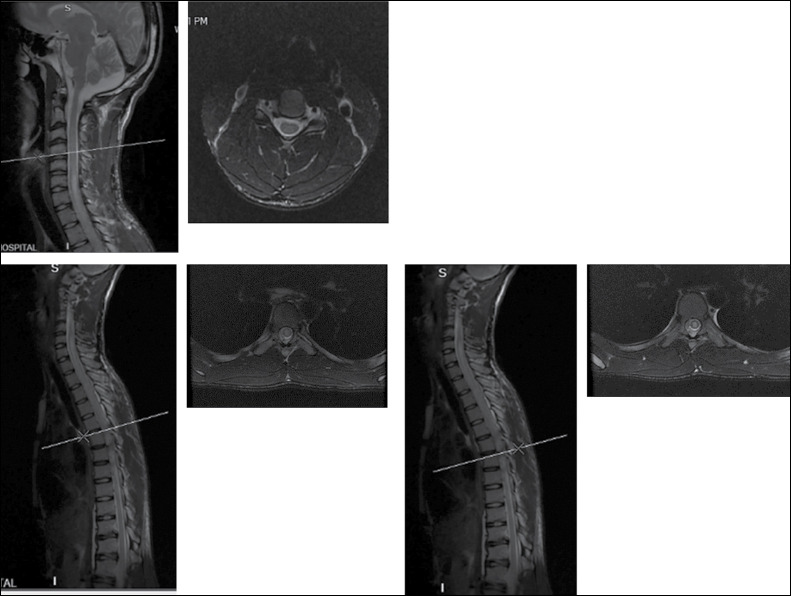

Spinal cord involvement is a rare complication of the schistosomiasis manifesting as myeloradiculopathy, medullary or conus-cauda equina syndrome which can lead to potentially serious long-term disability. Computed tomography and magnetic resonance imaging coupled with biochemical parameters have become the mainstay of diagnosis. Biopsy which is the gold standard of diagnosis demonstrating the organism is usually reserved for cases of diagnostic challenge. We report a rare case of upper thoracic spinal cord schistosomiasis diagnosed by biopsy in an 18-year-old male migrant presenting to a spine and orthopaedic centre in Ghana with complaints of upper back pain and associated myeloradiculopathy symptoms. Initial suspicion of intramedullary cord tumour was made based on magnetic resonance imaging findings warranting biopsy which revealed schistosoma spp. He was treated with anthelminthics and corticosteroids with a resolution of symptoms.